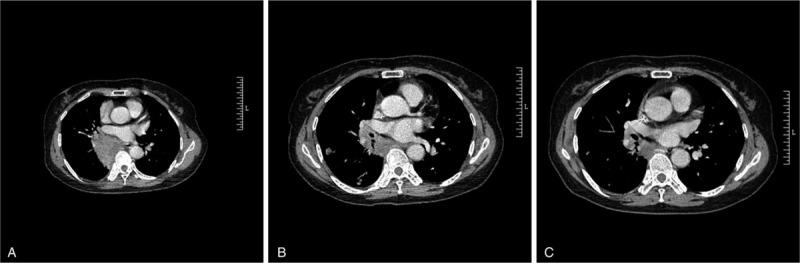

We report a case of a 64-year-old woman with a 20-day history of chest pain with computed tomography scan showing a right lower lung mass.

The patient was treated with sintilimab plus nedaplatin and paclitaxel as neoadjuvant therapy for 3 cycles, followed by right thoracotomy, right middle lobectomy, right lower lobectomy, hilar lymphadenectomy, mediastinal lymphadenectomy, and pericardiostomy.

The patient was discharged from the hospital 12 days after operation. Pathological report showed no cancer residue in the lung tissue, the bronchial stump, the anastomotic lung marginal tissue, 2nd, 4th, 7th, 9th, 10th, 11th lymph nodes or in the peribronchial lymph nodes after repeated sampling. The pathological stage was deemed T0N0M0. She remained disease free until the latest follow up in July 2019.